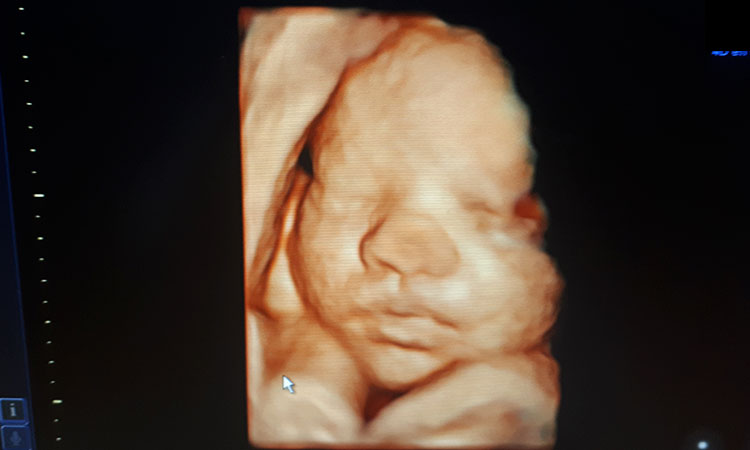

Lo siguiente son unas de nuestras ecografias realizadas:

Ecografia 4d

En el caso de la 4d el movimiento del feto a tiempo real. Esto permite hacerse una idea de la capacidad motora del bebé así como de su comportamiento general y respuesta a estímulos.

Las exploraciones 3D, 4D y 5D permiten realizar una reconstrucción volumétrica muy realista de las estructuras fetales en movimiento; permitiendo visualizar a tiempo real y generalmente de forma nítida la cara fetal, las extremidades y sus movimientos.

El mejor momento para realizar este tipo de ecografias corresponde especialmente a las semanas 25 a 30, ya que se podrán apreciar mejor los rasgos de la cara del bebé, los bostezos, como se chupa el dedo o mueve los brazos.